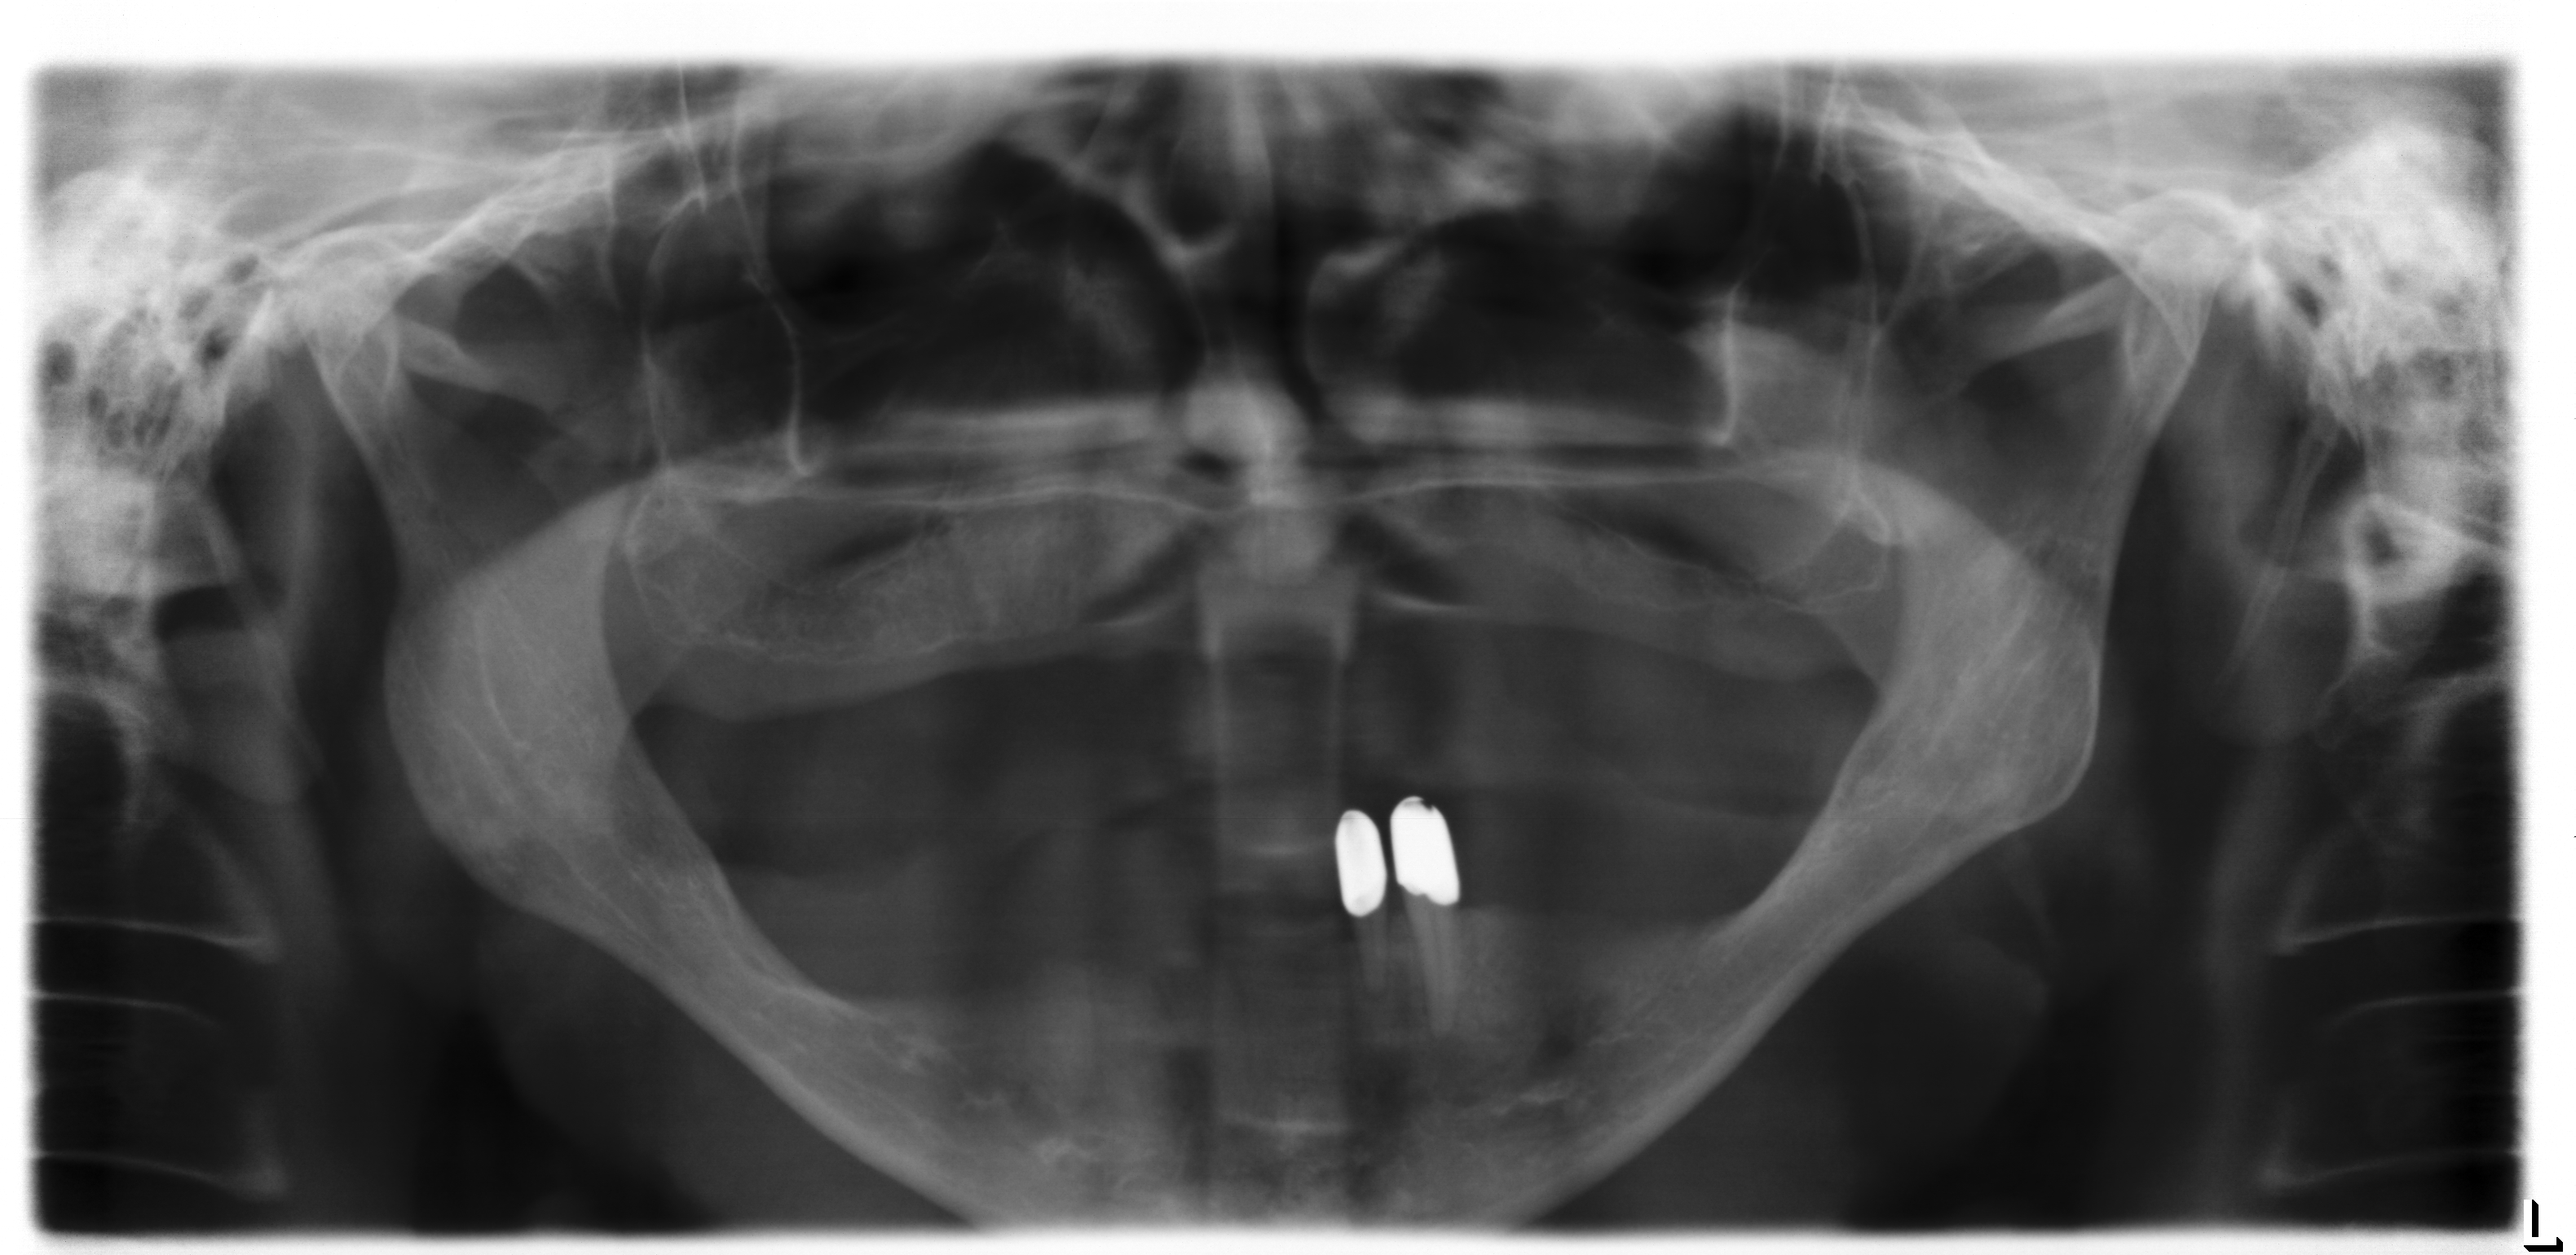

Die Ausgangssituation (Abb.1, Abb.2, Abb.3 ) zeigt einen im Oberkiefer zahnlosen (Abb.4) und im Unterkiefer mit zwei Restzähnen bezahnten Patienten (Abb.5). Der Patient leidet sehr stark unter dem fehlenden Halt der nicht mehr richtig sitzenden Oberkiefer- und Unterkieferprothesen. Diese führen für den Patienten zu einer stark verminderten Lebensqualität, da sowohl die Essensaufnahme, als auch die soziale Interaktion mit den Mitmenschen stark beeinträchtigt ist. Aufgrund des stark zurückgegangenen Knochenniveaus und dem damit verbundenen schlechten Prothesenlager, ist eine wirkliche Verbesserung der Gesamtsituation nur über zusätzliche Befestigung der Prothesen über im Knochen fixierte Zahnimplantate denkbar. Aufgrund des starken Knochenrückgangs sowohl im Ober- als auch im Unterkiefer, ist das Einbringen von Titan-Zahnimplantaten zur Stabilisierung der Prothesen nicht ohne aufwändigen Knochenaufbau möglich. Hierzu ist der Knochen den man innerhalb der Mundhöhle gewinnen kann nicht ausreichend und so bietet sich die Knochenentnahme im Bereich des Beckenkamms an.